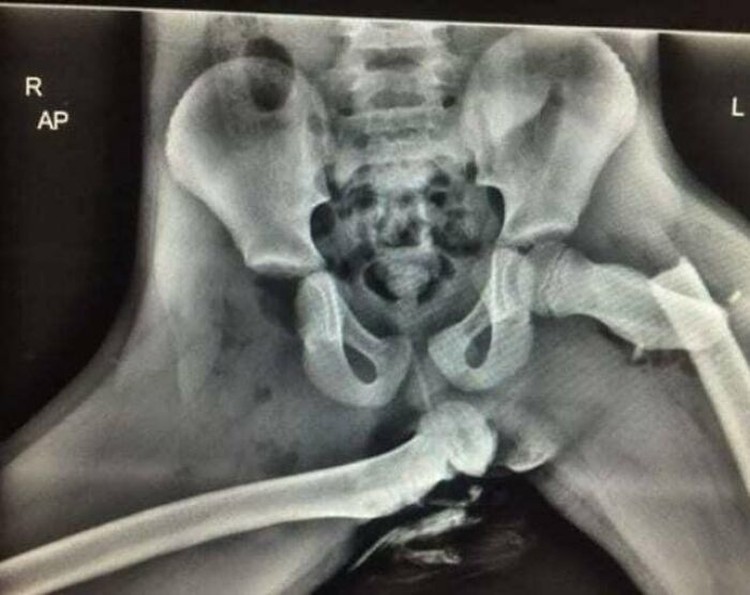

Kemudian, mereka memutar bagian bawah kaki 180 derajat dan menempelkannya ke pinggul, mengikat saraf dan pembuluh darah sehingga aman. Prosedur ini paling sering digunakan untuk memindahkan sendi pergelangan kaki ke sendi lutut setelah reseksi tumor tulang femoralis distal, seperti osteosarkoma. Foto: Medicalpedia via Boredpanda